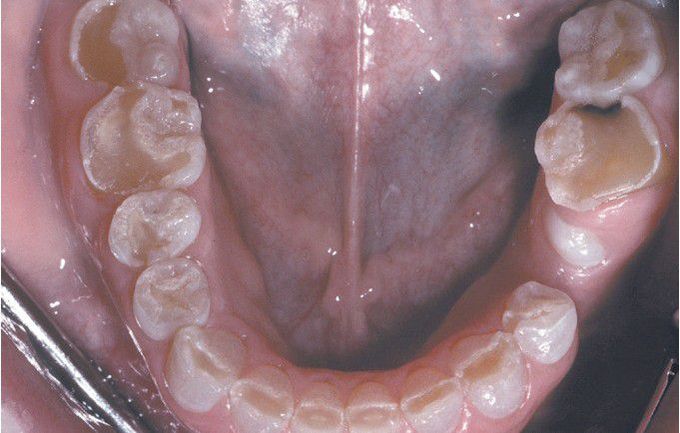

Dentinogenesis Imperfecta (DGI

Dentition exhibiting grayish discoloration with significant enamel loss and attrition.